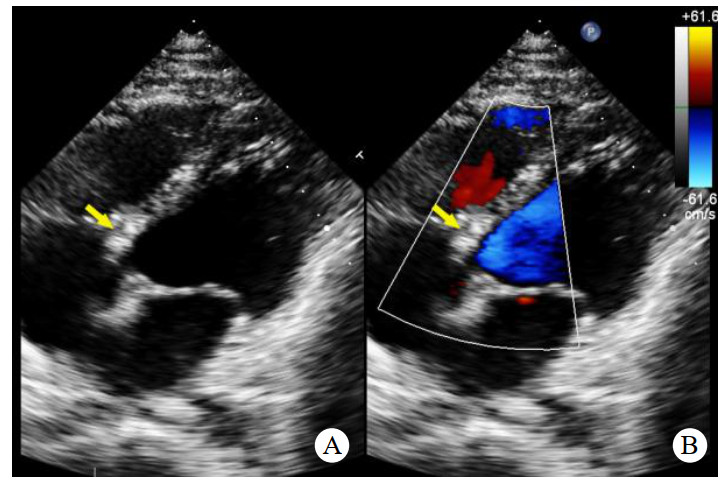

术前心脏计算机断层扫描血管造影(computed tomographyangiography, CTA)检查未能明确诊断右乏氏窦瘤破裂(图 4),这给临床医生带来一定困惑。经急诊超声心动图检查及临床医生全面评估后行右乏氏窦瘤破裂修复术和主动脉瓣成形术。取适当大小的牛心包补片,间断褥式缝合修补破口及室间隔夹层,并行主动脉瓣成形术。术中经食道超声心动图显示窦瘤破裂修补完好,分流消失,主动脉瓣瓣叶开闭良好,反流消失。术后1个月复查,二维超声心动图显示主动脉短轴切面:右乏氏窦瘤破裂修补处回声增强,连续性好;CDFI:该处分流消失。主动脉瓣瓣叶开闭正常。胸骨旁四腔心切面显示如上(图 5),室间隔回声稍不均质,室间隔夹层动脉瘤完全塌陷,未见夹层动脉瘤显示。

| 注:A为2D超声显示胸骨旁四腔心切面右乏氏窦瘤破裂修补处(黄色箭头)回声增强,连续性好;B为CDFI显示该处分流消失 图 5 2D及CDFI显示右乏氏窦瘤破裂修复术和主动脉瓣成形术后表现 |